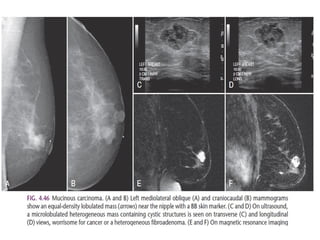

The shape of a mass is either round, oval or irregular.

Always make sure that a mass that is found on physical examination is

the same as the mass that is found with mammography or ultrasound.

The density of a mass is related to the expected

attenuation of an equal volume of fibroglandular tissue.

High density is associated with malignancy.

It is extremely rare for breast cancer to be low density.